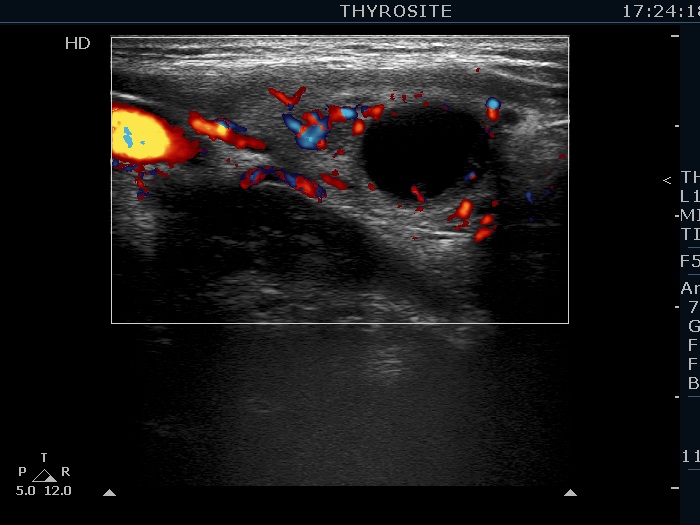

Ultrasonography. The thyroid was echonormal. There were several hypoechogenic lesions in the right lobe. The left lobe had an upper, solid and a lower cystic nodule. The former had both echonormal and moderately hypoechogenic parts and presented halo sign. The cystic nodule had a very tiny solid area in the dorsal part. Nonetheless, before aspiration it was unclear whether this would be a pure cyst or not. After aspirating 2 mL serous fluid a large, moderately hypoechogenic solid area replaced the previous cystic field and it became evident that this is in fact a central type cystic nodule.